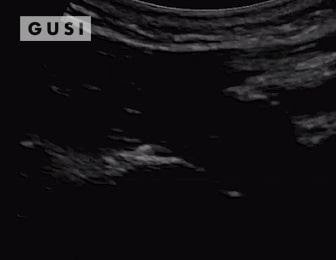

Case Study #3

During the 2017 World Taekwondo Championships in Muju, Korea, a 30-year-old female athlete from Hong Kong was kicked in her left eye by an opponent. She reported fluctuating vision accompanied by pain during eye movement. A POCUS examination of the affected eye indicated a vitreous hemorrhage, with no evidence of lens subluxation or globe rupture.

On the ultrasound, as the athlete moved her eyes laterally, the hemorrhage (denoted by a white arrow) exhibited a swirling pattern within the globe, consistent with her eye movement. The athlete was promptly referred to a specialized medical center for an ophthalmology consultation, where the diagnosis of vitreous hemorrhage was confirmed. The patient was subsequently discharged from the Emergency Department with specific precautionary measures.